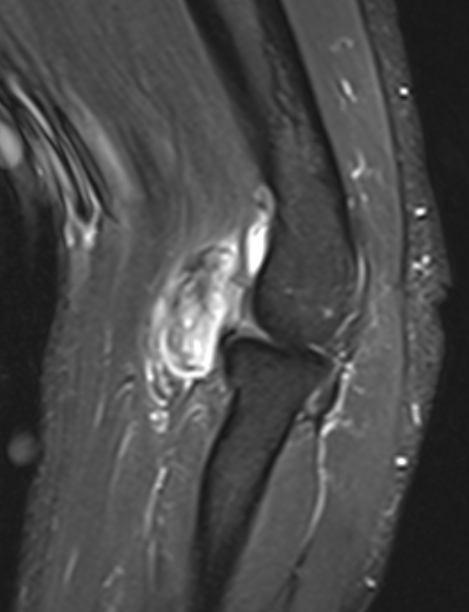

MRI

Heterogenous mass, low signal intensity T1, high signal intensity T2

- may have characteristic triple signal intensity

- area hyperintensity, isointensity and hypointensity

Knee

Heterogenous mass, not communicating with joint

DDx Baker's cyst